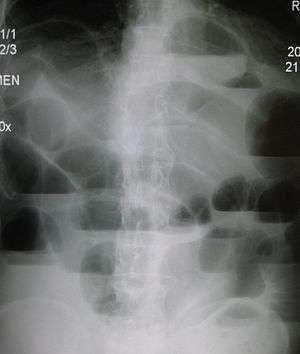

Radiological signs of bowel obstruction include bowel distension and the presence of multiple (more than six) gas-fluid levels on supine and erect abdominal radiographs.

According to a meta-analysis of prospective studies by the Cochrane Collaboration, the appearance of water-soluble contrast in the cecum on an abdominal radiograph within 24 hours of oral administration predicts resolution of an adhesive small bowel obstruction with a pooled sensitivity of 96% and specificity of 96%.[11]

Some causes of bowel obstruction may resolve spontaneously;[12] many require operative treatment.[13] In adults, frequently the surgical intervention and the treatment of the causative lesion are required. In malignant large bowel obstruction, endoscopically placed self-expanding metal stents may be used to temporarily relieve the obstruction as a bridge to surgery,[14] or as palliation.[15] Diagnosis of the type of bowel obstruction is normally conducted through initial plain radiograph of the abdomen, luminal contrast studies, computed tomography scan, or ultrasonography prior to determining the best type of treatment.[16]